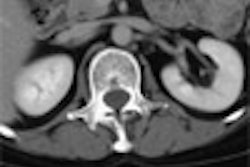

Computer-aided detection is a pillar of hope for virtual colonoscopy's future, representing the dual promises of easier patient prep and more consistent results for VC readers.

Large studies demonstrating CAD's reliability must precede regulatory approval for any system. As it so happens, a multicenter trial has been initiated to explore these issues, with promising initial results.

In this issue's Insider Exclusive, Dr. Luca Bogoni from Siemens Medical Solutions' CAD group reports on the early results of a VC CAD trial under way at 12 centers across the U.S. and Europe. Published results from the first 500 patients will show greater than 90% sensitivity for detecting clinically significant polyps, Bogoni said.